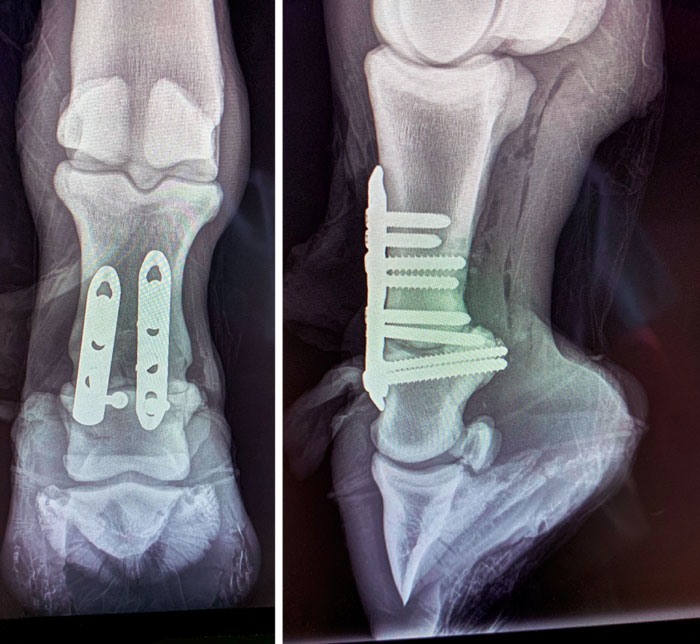

The excitement surrounding Peyton’s promising future came to a screeching halt just 2 months later when an accident left his career in jeopardy. Peyton suffered fractures to the short and long pasterns of his right hind leg, requiring surgeons to stabilize the bones with plates and screws.

Peyton fractured the short and long pasterns in his right hind leg. Photo: Mike Hachtel